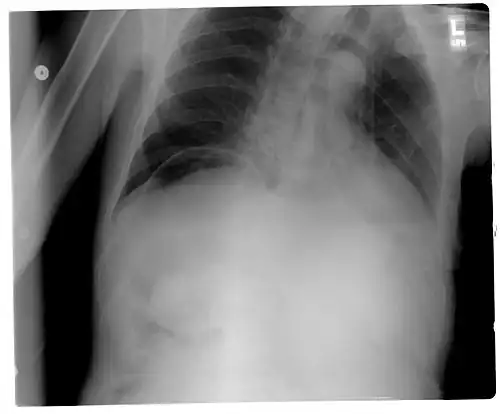

Pneumoperitoneum seen on X-ray with the patient lying on his left side. -